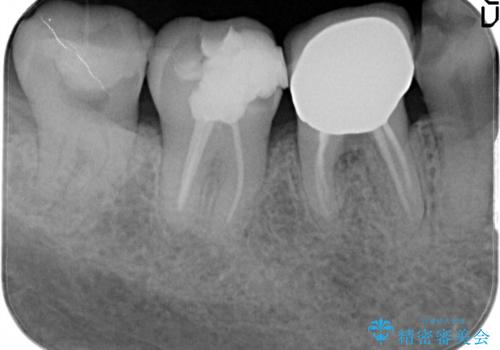

虫歯の治療 オールセラミッククラウン

- 他院にて以前治療した修復物の下に虫歯を認めたため、オールセラミックにて修復治療を行なっております。

オールセラミッククラウンは天然歯と同様に透明感を出すことができ、より審美的な治療が可能です。